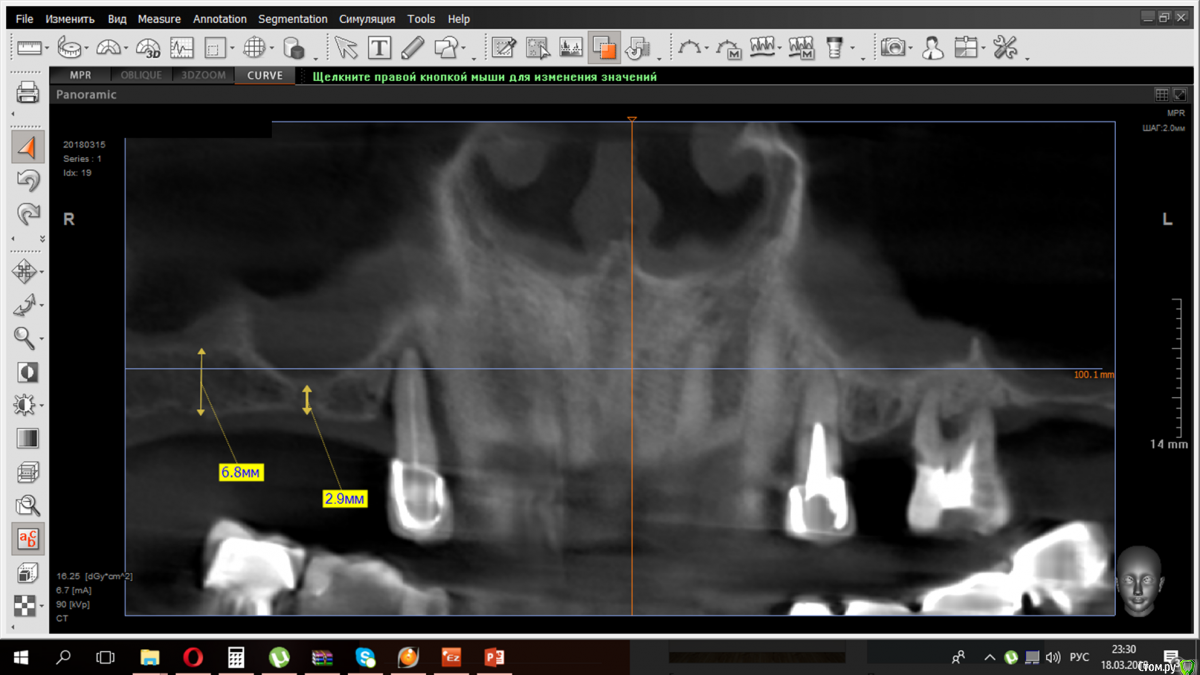

kramer Опубликовано 19 марта, 2018 Поделиться Опубликовано 19 марта, 2018 Коллеги, здравствуйте, каков алгоритм действий, если в рамках обследования перед СЛ в пазухах обнаруживается всякая ерунда? В каких случаях требуется предварительная санация пазух? Где об этом прочитать? Спасибо. Ссылка на комментарий

Карен Аванесов Опубликовано 19 марта, 2018 Поделиться Опубликовано 19 марта, 2018 (изменено) От части одонтогенная причина просматривается, можно удалить зубы и повторить КТ, если все хорошо делать синус, или после удаления и заживления направить уже к лору что бы одонтогенную природу исключить. Изменено 19 марта, 2018 пользователем Карен Аванесов 1 Ссылка на комментарий

kriokov Опубликовано 19 марта, 2018 Поделиться Опубликовано 19 марта, 2018 В каких случаях требуется предварительная санация пазух? согласен с Кареном. Санация нужна при разных ситуациях, но основное-- воспалительные изменения в пазухе с нарушением дренажной функции ( соустье надо смотреть) 1 Ссылка на комментарий

Борис80 Опубликовано 21 марта, 2018 Поделиться Опубликовано 21 марта, 2018 если есть возможность, сделайте срез чтобы было видно все носовые ходы( повыше) Ссылка на комментарий

kramer Опубликовано 21 марта, 2018 Автор Поделиться Опубликовано 21 марта, 2018 если есть возможность, сделайте срез чтобы было видно все носовые ходы( повыше)У пациента на руках только такая КТ была. Соустья не видно( Ссылка на комментарий

Sergiosse Опубликовано 23 марта, 2018 Поделиться Опубликовано 23 марта, 2018 если есть возможность, покажите срез где видно соустье Ссылка на комментарий